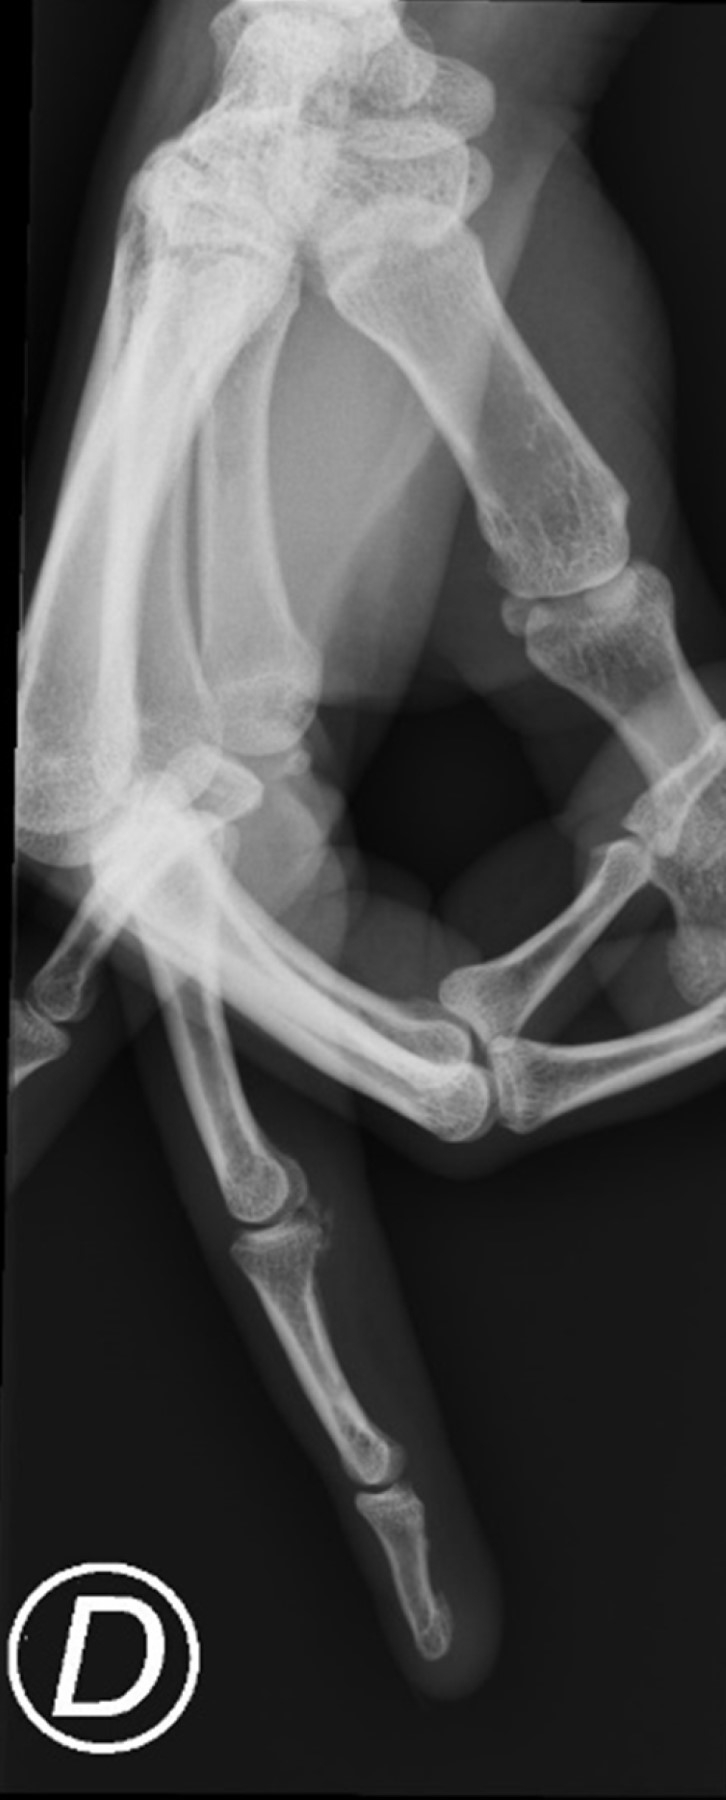

The patient was seen in an ambulatory setting one week after the episode, and she was already nearly free of symptoms. At reevaluation one month after the trauma, she had fully recovered in terms of pain and mobility. The calcification had practically disappeared on the radiograph (Figure 2).

One last appointment was scheduled nine months after the initial visit. The patient had no symptoms or limitation of the range of motion, and the plain radiograph showed no signs of calcification (Figure 3).